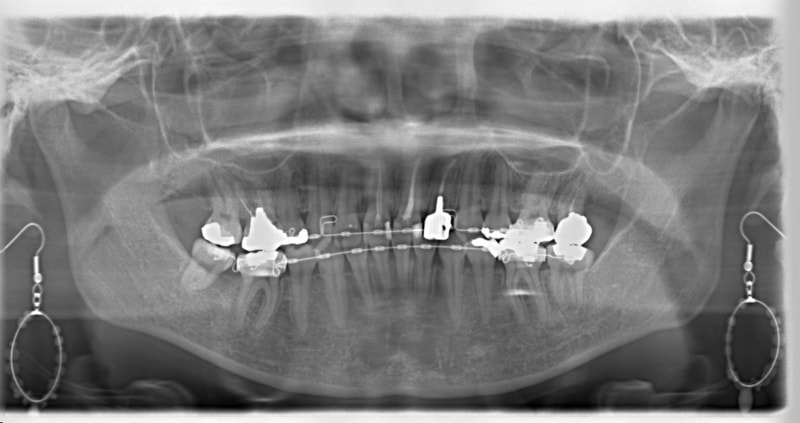

右下7番欠如歯(保存不可能歯につき抜歯)右下8番利用

治療法:フルパッシブブラケット:クリアスナップ

治療開始時